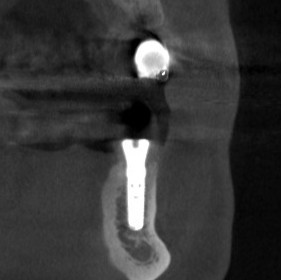

下の写真が、手術前後のCTです。